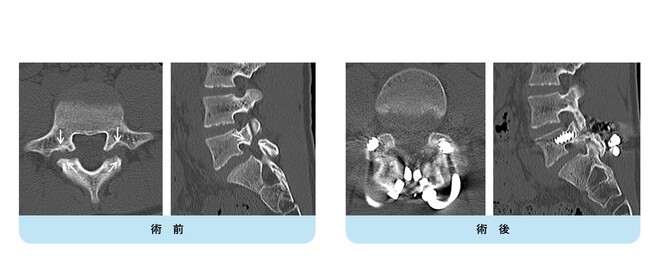

【術前】

CT検査で関節突起部に腰椎分離症を認めています。若年者の腰痛の原因となります。

【術後】

CT検査で関節突起部の骨移植を伴う分離部修復術を施行し骨癒合が得られています。